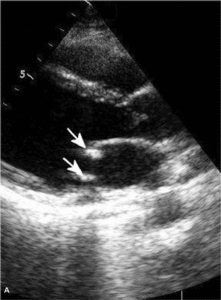

Toczeń rumieniowaty układowy

Zwiększone ryzyko zaburzeń zakrzepowo-zatorowych u chorych z toczniem rumieniowatym układowym wynika przede wszystkim z częstej obecności przeciwciał antyfosfolipidowych u tych chorych. W ostatnich badaniach wykazano, że zwiększone stężenie aCL i anty-ß2GPI w klasie IgG powodują wzrost ciśnienia skurczowego w prawej komorze (ryc. 3A, B) [11]. Stwierdzono także większą częstość występowania przeciwciał aCL u chorych z SLE i nadciśnieniem płucnym w porównaniu z chorymi z prawidłowym ciśnieniem w tętnicy płucnej [12]. W innym badaniu chorych z mieszaną chorobą tkanki łącznej (mixed connective tissue disease, MCTD) nadciśnienie płucne było związane ze zwiększonym stężeniem przeciwciał anty-ß2GPI [13]. Podwyższenie ciśnienia skurczowego w tętnicy płucnej związane z występowaniem przeciwciałami aCL może wynikać z mikrozakrzepicy lub mikrozatorowości, która zwiększa opory naczyń płucnych, powoduje wzrost ciśnienia skurczowego w prawej komorze i prowadzi do powiększenia prawej komory. Należy podkreślić, że względne ryzyko zatorowości płucnej u chorych z SLE w pierwszym roku od rozpoznania w porównaniu z populacją ogólną jest bardzo duże i wynosi 10,23 [14].